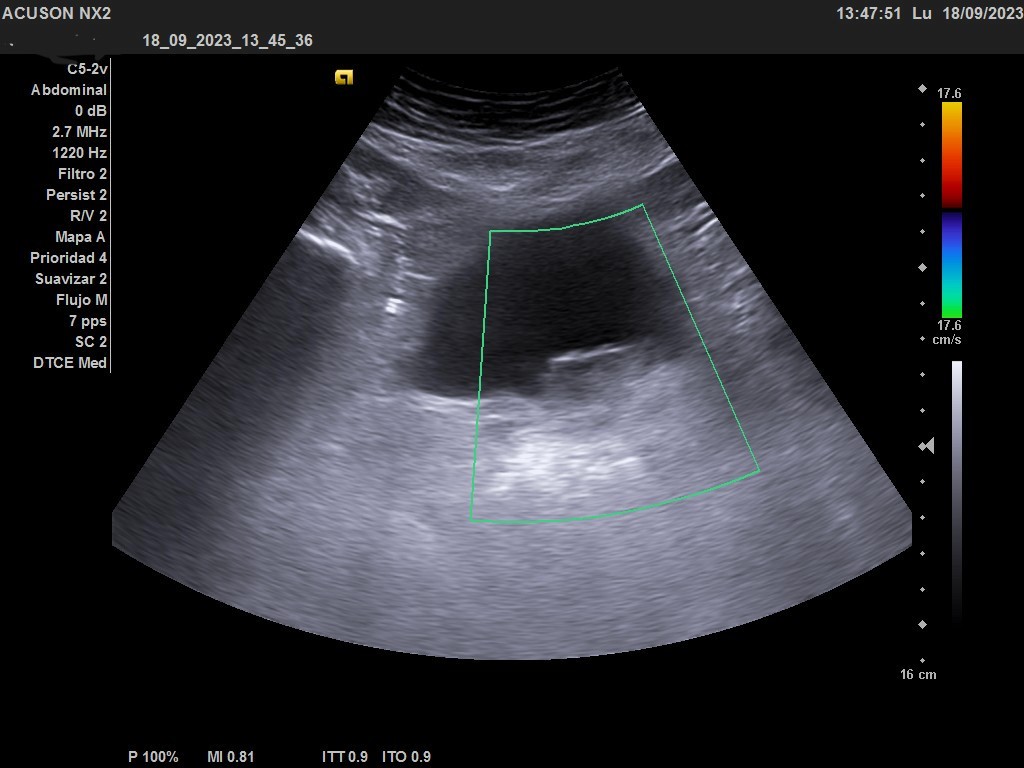

Ecografía clínica urológica: vejiga moderadamente replecionada. Se visualiza en pared posterior imagen hiperecogénica que no capta al Doppler color, de características sospechosas de malignidad. Riñones sin alteraciones en parénquima ni signos de hidronefrosis.

En la ecografía urológica reglada ambos riñones son de tamaño normal y parénquima conservado. La vejiga está replecionada, pero se identifica un engrosamiento nodular de 26 x 15 mm en la pared inferolateral izquierda, próxima al meato. Próstata de pequeño tamaño con un volumen de 7 cc.